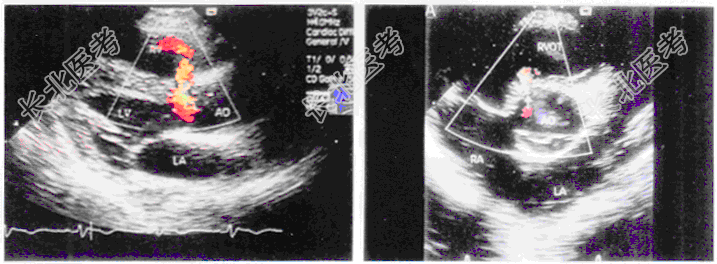

- 单项选择题患儿,1岁, 男,体检发现胸骨左缘全收缩期杂音, 超声检查如图所示。该图所示的室间隔缺损属于以下哪型

A、干下型

B、肌型

C、隔瓣下型

D、嵴内

E、膜部